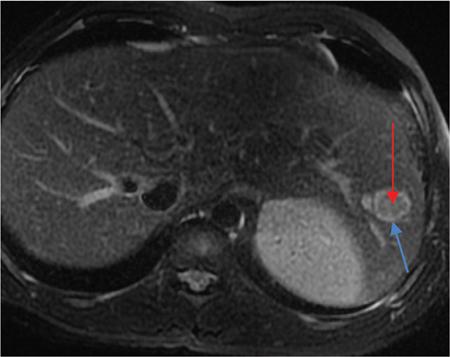

Ritu K. Kashikar, Shrinivas B. Desai, Pooja Punjani Vyas, Nilesh Doctor, Vivek Shetty Owing to advances in technology, focal liver lesions (FLLs) are increasingly encountered. Imaging particularly computed tomography (CT) and magnetic resonance imaging (MRI) play a vital role in diagnosis and characterization of FLL, thus avoiding unnecessary biopsies and interventions. Multiphase CT accurately diagnosis most liver lesions. Better soft tissue contrast and lack of ionizing radiation makes MRI a preferred modality in diagnosing FLLs. MRI with or without contrast for characterization of liver lesions regardless of preexisting liver disease has been assigned the highest rating as per American College of Radiology Appropriateness Criteria (Table 9.11.1). Solid lesions of epithelial origin Solid lesions of nonepithelial origin Pitfalls Cystic liver lesion Developmental cyst Infective cyst Miscellaneous Tmours of hepatocellular origin Tumours of nonepithelial origin Malignant cystic lesion Hepatic metastasis Ultrasound is often the initial modality for diagnosis and also the incidental detection of FLLs. Limitations to USG include the detection of small lesions less than 2 cm in size, particularly in patients who are cirrhotic or undergoing chemotherapy. Characterization of FLLs, involvement of crucial structures such as blood vessels, local staging and decisions such as operability are also not accurate with ultrasound alone and require confirmation with CT/MRI. The liver typically images in supine and left lateral positions. A curvilinear transducer with a frequency of 1.5 Hz is used. The subcostal diagonal, subcostal longitudinal or sagittal and transverse right intercostal lateral views are used. Right lobe of liver is imaged through an intercostal approach when the patient is taking deep inspiration. Subcostal view is used to image the three hepatic veins in one view. Transverse, longitudinal and oblique views of the liver are taken to image all the segments of liver. Colour and power Doppler have increased sensitivity for FLL detection, but sensitivity is still inferior to contrast-enhanced CT and MRI. The introduction of microbubble contrast agents (CAs) and the development of contrast-specific techniques have opened new perspectives in ultrasound of the liver. The technique is based on a new class of intravascular microbubble agents which contain perfluoro gases instead of air. This when combined with scanning modes sensitive to harmonic responses of microbubbles enable tissue signal suppression. The advent of the multislice technique and isotropic voxel have improved the spatial resolution of CT, allowing the recognition of small FLLs in difficult areas. Multislice CT has a sensitivity and specificity in the diagnosis of malignant FLLs of 63% and 64%, and 92 and 97%, respectively. Contrast media administration with dose based on the patient’s weight (approximately 600 mg iodine/kg of bodyweight), an iodine content of 350–400 mg/mL and a high injection rate of 4–5 mL/s are imperative to attain good contrast enhancement. Region of interest in the abdominal aorta and a threshold of 100 HU allows correct timing for threshold. A delay of approximately 18 s after the threshold provides the first arterial phase, allowing detection of hypervascular FLLs such as hepatocellular carcinoma (HCC). The late arterial phase is obtained approximately 10 s after the early arterial phase and shows progressive enhancement of hypervascular lesions, improving detection rate, while the optimal hepatic enhancement in the portal phase is reached approximately 50–60 s after the threshold. Portal venous thrombi are also best detected in this phase. The venous phase aids in the detection of washout, hepatic venous thrombosis. Delayed phase is often required in lesions such as cholangiocarcinoma and haemangioma, which show progressive enhancement (Table 9.11.2, Fig. 9.11.1). Delayed phase images are required for tumours such as cholangiocarcinoma and large haemangiomas, which reveal delayed enhancement. As mentioned previously, MRI is the modality of choice in diagnosis of FLLs. Most FLLs appear hyperintense on T2W1 images with varying intensity depending upon the water content and flow dynamics. FLLs are typically hypointense on T1W1 images with the exception of fat containing, haemorrhagic lesions and those containing chelates of metals like regenerating/dysplastic nodules. In- and opposed-phase images help in detection of intralesional fat. Diffusion-weighted images are beneficial particularly in noncirrhotic population and best suited in detection of metastasis. Postcontrast images obtained with extracellular agents are parallel to those obtained with CT (Fig. 9.11.2). The pre- and postcontrast MRI protocol is mentioned in Table 9.11.3. T2-weighted single-shot fast spin-echo (SE) T1-weighted in- and opposed-phase GRE Dynamic 3D T1-weighted FS spoiled GRE (in hepatic arterial, portal venous and equilibrium phases) There are two main categories of CAs used in liver imaging – the extracellular and the hepatocyte-specific (Fig. 9.11.3). Extracellular agents are more widely used and provide information similar to contrast-enhanced CT study. The advantage of the other category of CAs, that is, hepatocyte-specific agents, is the ability to provide this extracellular information with added benefit of delayed phase information. Tumours of hepatocellular origin with functioning hepatocytes take up and biliary excretion with take up and retain these agents appearing isointense to background liver. Lesions without functioning hepatocytes fail to retain contrast and hence appear hypointense to background liver on delayed phase. This allows better detection and characterization of focal liver lesion particularly those lesser than 2 cm (Table 9.11.4). Haemangioma is the most common benign hepatic tumour. The incidence in general population varies from 1% to 20%. Females have a higher preponderance with variable female to male ratios of 2:1 to 5:1. Imaging in particular MRI has high reliability in diagnosing classic haemangioma. The sensitivity and specificity of MRI is greater than 90% in diagnosis. The aetiology of haemangioma is unknown. Since haemangiomas are known to run in families, a genetic origin has been implicated, while other mesenchymal tumours are thought to be congenital. Most patients are asymptomatic and often the lesion is discovered as an incidental finding. Pain in the right upper abdomen is the most common complaint; others include loss of appetite, nausea, vomiting and abdominal discomfort. Symptoms are usually seen in large haemangiomas or those with complications. Liver function tests and tumour markers like AFP and CA19.9 are within normal limits. Blood-filled cavities of varying sizes lined by flat endothelial cells and supported by fibrous connective tissue are seen on histology. Three histological subtypes have been described: the capillary haemangioma, the cavernous haemangioma and the sclerosing haemangioma. The imaging features of a haemangioma depend on its size; typical haemangiomas are mostly less than 3 cm in diameter. Haemangiomas are hyperechogenic, homogeneous lesion presenting a posterior acoustic enhancement (Fig. 9.11.3). The hyperechogenicity of haemangiomas is related to the interfaces between vascular spaces, fibrous stroma and the slow blood flow. Typically, haemangiomas have slow flow and hence do not show vascularity on colour or power Doppler. The sensitivity and specificity of ultrasound in differentiating haemangioma from other malignant lesions are high, with values of approximately 94.1% and 80%, respectively, for lesions less than 3 cm in diameter. Unlike HCC, no flow is seen on colour Doppler. A peripheral echogenic rim around hypoechoic lesions can suggest haemangioma. On the contrary, perilesional hypoechoic rim called the target sign is seen in lesions such as metastasis (Table 9.11.5). Adenomas can be distinguished on the basis of the absence of posterior acoustic enhancement and characteristic pattern of peripheral vascularity seen in adenoma. Another differential diagnosis to be considered is focal nodular hyperplasia (FNH), which has the characteristic ‘spoke-wheel sign’. Contrast-enhanced ultrasound (CEUS) improves specificity for the diagnosis of haemangioma. The vascularity pattern with contrast-enhanced USG is similar to that seen with CT. The typical hemangioma (HH) shows peripheral nodular enhancement in the arterial phase with complete (but sometimes incomplete) centripetal filling in the portal venous and late phases. This particular pattern of enhancement helps in differentiating haemangiomas from other lesions like adenomas, FNH, HCC or metastasis. This characteristic enhancement pattern has a sensitivity of 98% for histologically proven HH. One should be aware that an HH can rarely have a centrifugal enhancement. Computed tomographic (CT) findings consist of a hypoattenuating lesion on nonenhanced images. Haemangiomas show peripheral discontinuous nodular enhancement on arterial phase of dynamic contrast-enhanced CT. The density of the nodules is equivalent to that of the aorta. Centripetal filling with is seen on venous phase, which progresses to uniform enhancement. The enhancement persists on delayed phase (Fig. 9.11.4). Washout of contrast on delayed phase is not seen in haemangioma and if seen, alternate diagnosis must be considered. This classical pattern of enhancement cannot be highlighted in very small lesions of less than 5 mm, which can be difficult to characterize. In patients with severe fatty infiltration of the liver, HH can appear hyperdense relative to the adjacent liver parenchyma on nonenhanced scan. Haemangiomas are hyperintense on T2-weighted images, which is identical to that of cerebrospinal fluid. T2 hyperintense signal is classically described as ‘light bulb bright’. Malignant lesions of the liver do not appear as bright on T2W1 images. They appear hypointense to adjacent liver on T1-weighted images. Long relaxation T2W1 images further improve accuracy in diagnosis of haemangiomas and help in differentiation from metastasis. Haemangiomas, unlike other liver lesions retain hyperintense signal on long relaxation T2W1 images. A threshold of 112 ms has 92% accuracy, 96% sensitivity and 87% specificity for differentiating haemangiomas from metastasis. On gadolinium administration, the enhancement pattern is similar to that seen with iodinated contrast on CT. Classic enhancement pattern in combination with characteristic T2 appearance are diagnostic for haemangioma (Fig. 9.11.5). Certain pitfalls exist in diagnosing haemangiomas using gadoxetate disodium. Due to the lack of hepatocytes, haemangiomas appear hypointense to the background liver on delayed hepatocyte phase and mimicking malignant process (Table 9.11.6). Lesions shown peripheral nodular arterial enhancement (Table 9.11.7): On fluorodeoxyglucose-positron emission tomography (FDG-PET)/CT, most hepatic haemangiomas appear low-attenuation lesions with FDG avidity equal to background liver parenchyma and are easily determined to be benign. However, a small percentage of haemangiomas may be FDG-avid. If an FDG-avid hepatic lesion demonstrates the characteristic enhancement pattern, this is consistent with an FDG-avid haemangioma. Technetium-99m pertechnetate-labelled red blood cell scintigraphy has high specificity in the diagnosis of haemangiomas. In this technique, there is decreased activity in haemangiomas on early images and increased activity on delayed blood pool images. Therefore, radionuclide scintigraphy has a sensitivity of 78% and an accuracy of 80% and may be a valuable tool when the diagnosis cannot be achieved with other imaging modalities. Large haemangiomas are often heterogeneous with internal clefts and septae. They are termed as giant haemangiomas when they exceed 4 cm in diameter. Discrepancies are there in definition with some authors defining giant haemangiomas as lesions greater than 6 cm or 12 cm in diameter. These may cause symptoms of abdominal pain and distension. These haemangiomas demonstrate changes such as haemorrhage, thrombosis, extensive hyalinization, liquefaction and fibrosis. The central cleft-like area may be due to cystic degeneration or liquefaction. On USG, they reveal heterogeneous echotexture. They are hypoattenuating and heterogeneous on nonenhanced CT with central areas of low attenuation. After intravenous administration of contrast material, the typical early, peripheral and globular enhancement is observed. These may show irregular or ‘flame-shaped’ discontinuous peripheral enhancement as opposed to typical nodular enhancement pattern seen in smaller haemangiomas. Although centripetal pattern of enhancement is seen during the venous and delayed phases, the filling-in incomplete. Central scars are defined in this subset of haemangiomas (Fig. 9.11.6). At MRI, T2-weighted images show a markedly hyperintense cleft-like area and some hypointense internal septa within a hyperintense mass. On delayed phase, incomplete filling and central scar are seen similar to CT (Fig. 9.11.7). Complications include intratumoural haemorrhage, inflammatory changes or consumptive coagulopathy (Kasabach–Merritt syndrome). These may warrant management such as arterial embolization or resection. This pattern is seen 16% of all haemangiomas, and is seen more often in small haemangiomas (42% of haemangiomas) <1 cm in diameter. CT and MRI show immediate homogeneous enhancement at arterial phase CT or contrast-enhanced MRI. The size of the blood spaces is the reason for difference in enhancement pattern. Smaller the lesion, smaller the size of blood spaces and faster the rate of spread of contrast material. These lesions usually show perilesional halo of hyperenhancement on the late arterial phase, which is believed to be due to arteriovenous shunting. Rapid arterial enhancement makes these haemangiomas difficult to distinguish from hypervascular metastasis (Table 9.11.8). However, washout of contrast is seen from haemangiomas on delayed phase (Fig. 9.11.8). Hepatic haemangiomas rarely demonstrate calcifications, while haemangiomas in other locations frequently demonstrate phleboliths. Calcified haemangiomas are mostly found incidentally. Calcifications may occur in the marginal or central portion of the lesion and consists of multiple spotty calcifications, which correspond to phleboliths. However, large, organized calcifications are also possible. Some calcified haemangiomas may demonstrate poor enhancement. Hyalinized hepatic haemangiomas are rare. It has been suggested that hyalinization represents an end stage of haemangioma evolution. These haemangiomas are usually asymptomatic. The radiological features of a haemangioma are completely altered ones hyalinization occurs; hence biopsy is often mandatory for diagnosis. Hyalinized haemangiomas show only slight high signal intensity on T2W1 images. There is lack of early enhancement on dynamic contrast-enhanced images (Fig. 9.11.9). Fluid–fluid levels within haemangiomas are very rare. Fluid–fluid levels are seen both with CT and MRI with inferior layer representing the red blood cells and superior layer unclotted serous blood. Dependent hyperdensity/T1 hyperintensities can be seen corresponding with dependent haemorrhage. Pedunculated haemangiomas are very rare. They can be asymptomatic or complicated by subacute torsion and infarction. Typical enhancement pattern and signal on T1 and T2W1 images are clues to the diagnosis. Capsular retraction is usually associated with malignant tumours such as cholangiocarcinoma, epithelioid haemangioendothelioma or metastases. Rarely, it has been seen in haemangiomas. A possible mechanism could be fibrous degeneration. Multiple haemangiomas are seen in 10% of cases and usually show classical imaging features. Fatty infiltration of liver may alter the imaging appearances of lesions. Haemangiomas appear slightly hyperechoic, isoechoic or hypoechoic relative to the fatty liver. At nonenhanced CT, the lesion may be hyperattenuating relative to the liver. Contrast-enhanced CT shows peripheral enhancement and delayed filling, an appearance similar to that of a haemangioma in a normal liver. Haemangiomas are less common in setting of cirrhosis and may be difficult to diagnose due to sclerosis. Complications are seen in 4.5%–19.7% and often seen in large lesions such as inflammation, coagulation within can lead to systemic disorders, haemorrhage would lead to haemoperitoneum, volvulus and adjacent organ compression. Irrespective of the size, treatment is indicated only for haemangiomas with significant symptoms, those developing complications, or when there is an inability to exclude malignancy. Attempt should be made to exclude other causes of the patient’s symptoms. The term focal nodular hyperplasia (FNH) was introduced in 1958 by Edmondson. In 1995, the International Working Party classified FNH with other regenerative lesions, and not a neoplastic lesion. It is defined as a nodule consisting of normal appearing hepatocytes occurring in a histologically normal liver. It is the second most common tumour of the liver after haemangioma with a reported prevalence of 0.9%. The lesion is more commonly seen in females with female to male ratio of 8:1. Multiplicity is seen in 20% of patients. The combination of multiple FNH lesions and haemangiomas is considered to be multiple FNH syndrome. Vascular malformation and vascular injury have been suggested as the underlying mechanism. An association with steroids has been denied more recently. FNH has been classified as classic and nonclassic varieties. These have been discussed in Table 9.11.9. Classic FNH is characterized by abnormal nodular architecture, malformed vessels and cholangiolar proliferation. Nonclassic FNH lesions lack one of the following classic features – nodular abnormal architecture or malformed vessels – but always show bile ductular proliferation. Classic FNH on gross appearance shows lobulated contours with multiple nodules surrounded by fibrous septae originating from a central scar, which contains a vascular malformation. On histopathology, nodular hyperplastic parenchyma is seen in classic FNH. Circular or short fibrous septae surround these nodules completely or incompletely. Thickening of the hepatic plates is seen. Fibrous connective tissue, cholangiolar proliferation with surrounding inflammatory infiltrates and malformed arteries, capillaries, vascular channels of undetermined type and veins are seen in the central scar. The arterial blood in FNH shows centrifugal distribution from anomalous central arteries. Fatty infiltration is seen in approximately 50% of lesions, while signs of hepatic steatosis are seen in approximately 20% of cases with classic FNH. Variable amounts of Kupffer cells are seen in both classic and nonclassic variants. Nonclassic FNH is heterogeneous and on gross appearance resembles adenomas in most cases, with vaguely lobulated contours and lack of a macroscopic central scar. The histology varies with subtypes. Subtypes of nonclassic FNH include telangiectatic type, mixed hyperplastic and adenomatous forms and FNH with cytologic atypia. The histological features of these are described in Table 9.11.10. At US, typical FNH is often not well visualized. The lesions may be slightly hypoechoic, isoechoic or slightly hyperechoic. The compressed liver tissue form a hypoechoic halo around the lesion, which appears more prominent in patients with fatty infiltration. A prominent central scar may improve the conspicuity of the lesions. Use of colour and power Doppler US shows vascularity in suspected FNH. On contrast-enhanced USG, FNH is hyperenhancing in the arterial and portal venous phases in more than 90% of cases. The arterial enhancement patterns include central (60%–70% of cases) or eccentric (<20% of cases) with centrifugal filling, but sometimes are homogeneous. Multiphase CT is an excellent modality for detection and characterization of FNH. These lesions classically show a lobulated contour. At unenhanced CT, the lesions are either hypoattenuating or isoattenuating to the surrounding liver. In the arterial phase, the lesions show homogeneous intense enhancement except the central scar and fibrous septa. In the portal and later phases, the lesions become more isoattenuating with the surrounding liver. The central scar reveals enhancement on delayed phase (Fig. 9.11.10). This feature helps distinguish from other lesions with central scar-like fibrolamellar carcinoma. A vascular malformation can be seen in the central scar in some cases (Fig. 9.11.11). There may be enlarged hepatic veins in the vicinity of the mass. FNH do not have portal venous drainage. The drainage is essentially into hepatic venules, hence the enlarged adjacent veins. The central scar is often not identified in small FNH lesions. In a study, 80% of FNH lesions less than 3 cm lacked visible central scar. The sensitivity and specificity of MRI in diagnosis of FNH are 70% and 98%, respectively. The central scar is more often detected with MRI than with CT (78% and 60%, respectively). FNH is typically iso- or hypointense on T1-weighted images (94%–100%) and is slightly hyperintense or isointense on T2-weighted images (94%–100%). The lesions may not be very conspicuous on T2W1 images. The central scar is hyperintense on T2-weighted images in 84% of cases. FNH shows intense homogeneous enhancement in the arterial phase. The enhancement pattern in arterial phase may be nodular, resembling a popcorn, the result of intralesional fibrous septae. Mosaic pattern of heterogeneous enhancement seen in malignant lesions is not seen in FNH. Central vascular malformation may be seen in early phases. These lesions classically fade to isointensity on delayed phase with the exception of the central scar (Fig. 9.11.12). FNH may show a pseudocapsule, which results from compression of the surrounding liver parenchyma by the FNH, perilesional vessels and inflammatory reaction. The pseudocapsule may show enhancement on delayed contrast-enhanced images. A central scar is present at imaging in most patients with FNH. The central scar is hyperintense on T2W1 and hypointense on T1W1 images. The presence of inflammation and vessels within the scar are responsible for the hyperintense signal (Fig. 9.11.13). The scar does not enhance on early phases of contrast study and shows enhancement on delayed phases of dynamic study. The scar is absent in 30% of cases. The hepatocyte-specific CA gadoxetate disodium can be useful in distinguishing FNH from other lesions like adenomas. Densely packed functioning hepatocytes and abnormal blind-ending bile ductules in FNH result in contrast retention and delayed biliary excretion. FNH often shows enhancement on delayed images using gadoxetate disodium, and along with radiating fibrous septae, it may result in a characteristic spoke-wheel appearance. On the contrary, hepatocellular adenomas (HCAs) are usually hypointense to liver on hepatocyte phase images because they lack bile ductules. Superparamagnetic iron oxide (SPIO) is a negative reticuloendothelial-specific CA taken up primarily by the hepatosplenic Kupffer cells. This agent shortens T2 relaxation time predominantly, leading to a significant decrease of SI of normal hepatic. FNH contains Kupffer cells and hence shows significant signal drop after administering SPIO. This CA is, however, not commonly used particularly with advent and increased usage of hepatocyte-specific agents (Table 9.11.11). These lesions have high signal intensity on T2-weighted images, a central scar with low signal intensity on T2-weighted images, a prominent pseudocapsule and incomplete intense enhancement of the lesion. Extreme heterogeneity can be seen in these lesions leading to difficulty in distinguishing from malignant lesions such as HCC and cholangiocarcinoma. Biopsy and histopathology diagnosis are often needed in this subset. Telangiectatic FNH may show areas of haemorrhage. A French study has reported an association of 23% between FNH and haemangiomas. The incidence of coexistence of FNH and adenoma is lower (3.6%). There have also been reports of rare associations of FNH with other types of vascular anomalies like congenital absence of the portal vein, inflammatory pseudotumours of the liver, hepatic vein thrombosis and intrahepatic arteriovenous shunting. Imaging differentials include HCA and other lesions with central scar like fibrolamellar carcinoma, HCC and giant haemangiomas (Table 9.11.12). FNH shows intense arterial phase enhancement and isodensity/isointensity on delayed phase, this feature helps in distinguishing from adenoma, which usually are hypoattenuating on the delayed phase. T1 hyperintensity seen in adenomas is not seen on FNH. Biopsy is recommended in cases where radiological features are atypical and distinguishing from malignant lesions like HCC cannot be made on the basis of imaging findings alone. As there is no risk of malignant transformation and complications are rare, FNH does not need treatment. Patients with large FNH causing compression of adjacent organs or occurrence of torsion in a pedunculated FNH may need surgical resection. Also, patients with diagnostic dilemma may be considered as surgical candidates. Adenoma is a less common benign primary neoplasm of the liver. Women of childbearing age taking oral contraceptives are considered at highest risk; however, it can occur in other women as well as men. Hepatic adenomas (HAs) were particularly associated with the use of older generation of OC pills with high-oestrogen content. Adenomas have also been reported to occur in men secondary to anabolic steroid/androgen use. Clomiphene, danazol and testosterone in patients with Fanconi anaemia (FA) and without FA, Klinefelter’s syndrome, glycogen storage disorders (GSDs) I, III and IV, alcohol and metabolic syndrome are other hormonal therapies and conditions associated with adenoma. Development of >10 adenomas in a patient is defined as hepatocellular adenomatosis (Fig. 9.11.14). Germline mutations of hepatocyte nuclear factor (HNF)-1 alpha and patients with type 3 maturity onset diabetes of young (MODY-3) may predispose. HCA has been categorized into three distinct subtypes based on genetic and pathologic features. These have been discussed in Table 9.11.13. Some exhibit both β-catenin activation and inflammatory features. Patients are usually asymptomatic at the time of diagnosis but some present with abdominal pain, haemorrhage, abnormal liver function tests or seldom with a palpable mass. HCA associated with haemorrhage may present with acute abdominal pain, elevated liver enzymes and hypovolemic shock. Signs of chronic anaemia and/or ‘systemic inflammatory syndrome’, characterized by fever, leukocytosis and elevated serum levels of C-reactive protein can be seen in patients with inflammatory HCA. Inflammatory HCAs are associated with a definitive increased risk of bleeding (>30%) and a risk of malignant transformation (5%–10%). The highest predilection for malignant transformation of all HCAs is seen in β-catenin activated subtype. On gross appearance, adenomas are well-circumscribed often encapsulated lesions with size varying between 1 and 30 cm. Lesions may be solitary or multifocal. They typically arise in nonfibrotic liver, however, the inflammatory subtype has been reported in the background of cirrhosis The cut surface of HA may be tan-yellow or red-brown depending upon the presence of steatosis or peliosis/haemorrhage/old haemorrhage, respectively. Sheets of benign-appearing hepatocytes with interspersed thin-walled, unpaired arteries are classically seen in HCA. Other variable features are steatosis, inflammatory cell infiltrate, sinusoidal dilatation, myxoid changes and presence of pigments such as bile pigment, lipofuscin or Dubin–Johnson-like pigment (Table 9.11.14). The typical small HCA is isoechoic in comparison to the surrounding liver parenchyma. Adenomas with high lipid content are hyperechoic on ultrasound. Intratumoural haemorrhage can also result in increased echogenicity and heterogeneity, or cystic areas. Calcifications are seen as hyperechoic foci with acoustic shadowing. Peripheral peritumoural vessels and intratumoural vessels with a flat continuous or triphasic form are seen on colour Doppler. FNH does not show this pattern of vascularity and hence this finding may be useful in distinguishing the two disease entities. On contrast-enhanced USG, arterial phase reveals centripetal or diffuse enhancement. Telangiectatic HCA with or without inflammation typically exhibit iso- or hyperenhancement in comparison to the surrounding liver parenchyma. Hypoenhancement is seen in portal venous phase with delayed washout in all subtypes. USG and contrast-enhanced USG features of histologic subtypes have been described. HNF-1α-inactivated HCAs are hyperechoic due to fat content and may be misdiagnosed as haemangiomas. The enhancement pattern is however that of arterial enhancement. With venous washout in contrast to haemangiomas which show portal venous hyperenhancement. On CEUS, telangiectatic HCA with or without inflammatory changes shows central multilocular vessel supply similar to FNH. These lesions might show centrifugal hyperenhancement during the early arterial phase which may persist on portal venous phase. Nevertheless, most adenomas are not specifically diagnosed at US and are usually further evaluated with CT or MRI. Multiphase CT is a good diagnostic modality in diagnosis of HCA. Fat or haemorrhage can easily be identified on unenhanced images. CT evidence of fat within the adenoma is seen in only about 10% of cases. Lesions show strong arterial enhancement and subcapsular feeding vessels. Enhancement is more heterogeneous in larger tumours and those with internal haemorrhage. The enhancement usually does not persist in adenomas because of arteriovenous shunting (Fig. 9.11.15). MRI is the modality of choice in diagnosis of adenomas and distinguishing various subtypes. Although the lesions can reveal varying signal on T1W1 images, recent reports have suggested that most adenomas are bright on T1-weighted images, 77% of cases in a study by Paulson et al. Other studies have, however, lesser incidence of T1 hyperintensity varying from 35% to 59%. Heterogeneous signal on TW1 images may be due to areas of increased signal intensity resulting from fat (36%–77% of cases in different series) and haemorrhage (52%–93%). Forty-seven to seventy-four per cent of HCAs are predominantly hyperintense relative to liver on T2-weighted images (Fig. 9.11.16). Majority of lesions are, however, heterogeneous owing to areas of haemorrhage and necrosis. Contrast-enhanced dynamic MR study shows early enhancement with peripheral subcapsular vessels. MR appearances can vary depending on the histological subtype (Table 9.11.15). On plain MRI, inflammatory HCA is often hyperintense on T2W images and hypointense on T1W sequence corresponding to areas of sinusoidal dilatation and inflammatory infiltrates. Foci of fat appear as areas of signal drop on opposed-phase images. They are hypervascular masses with persistent enhancement on dynamic study. Variable update of contrast especially at the periphery may be seen on hepatobiliary phase. Marked T2 hyperintense signal with persistent delayed enhancement has high sensitivity and specificity of 85% and 87%, respectively, for the diagnosis of inflammatory subtype. Peripheral hyperintensity on T2W1 images reflects the abnormal ductal reaction with altered biliary excretion and has been described as ‘atoll sign’ (Fig. 9.11.17).